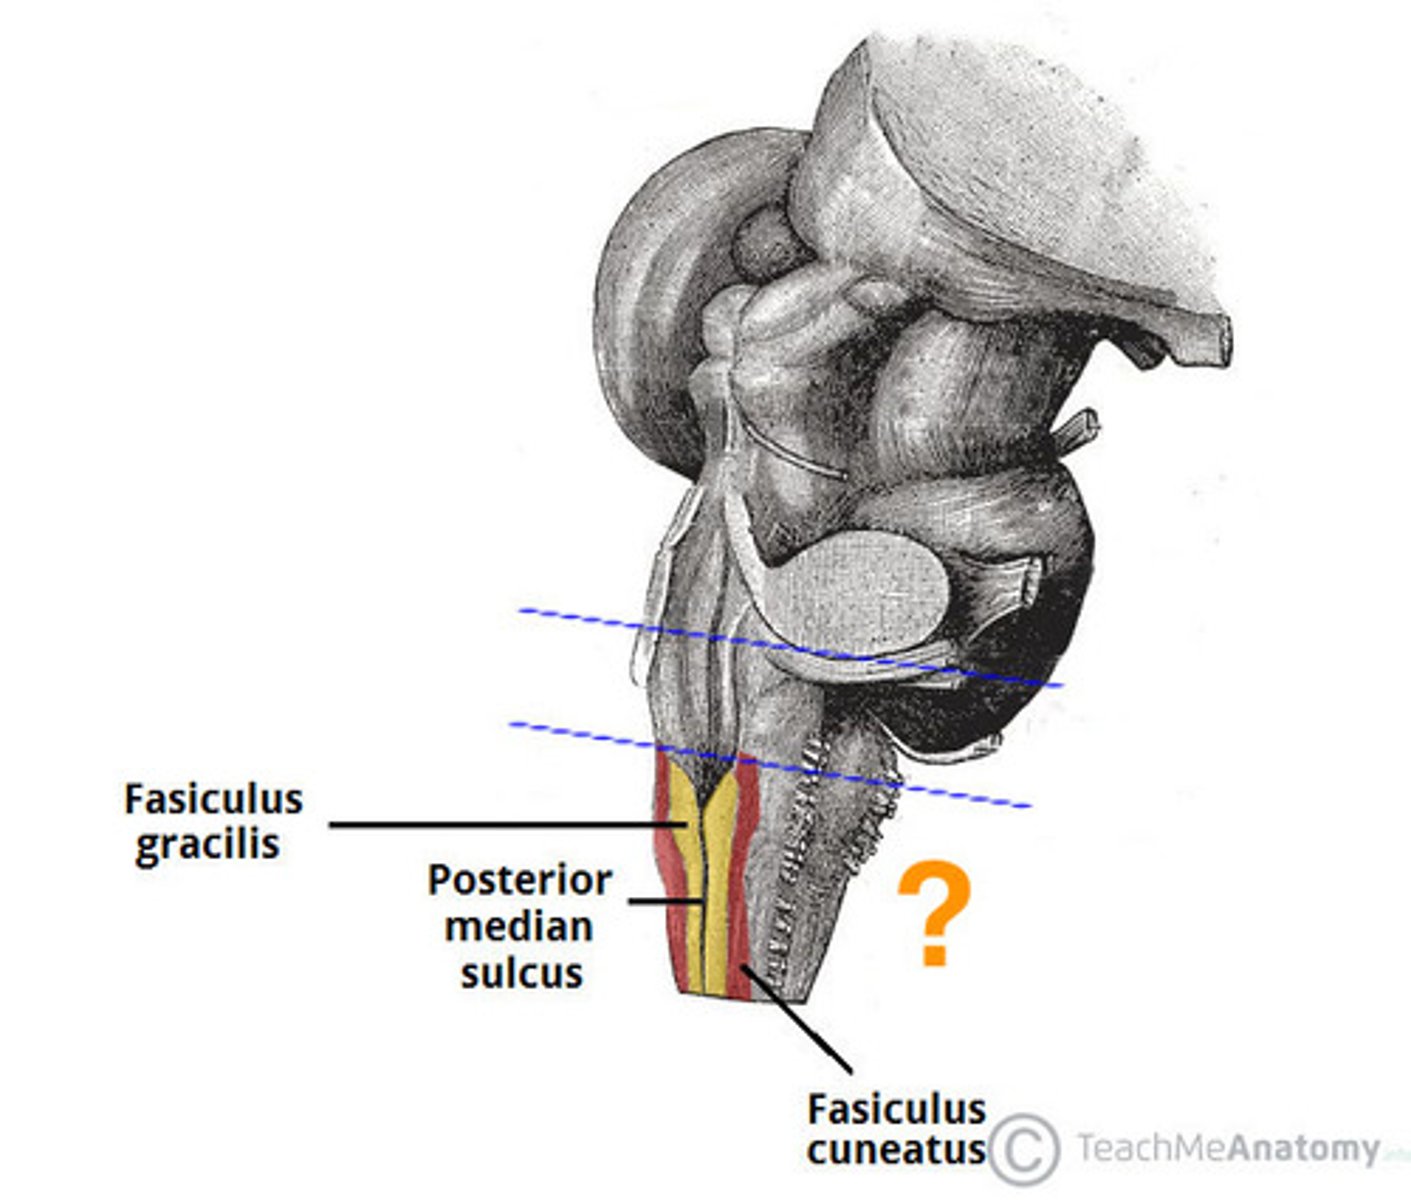

medial paired ridges of tissue on the dorsal aspect of the closed portion of the medulla

tractus gracilis

lateral paired ridges of tissue on the dorsal aspect of the closed portion of the medulla

tractus cuneatus

superior ends of the medial paired ridges of tissue on the dorsal aspect of the closed portion of the medulla, formed by namesake nuclei

gracilis tubercles

superior ends of the lateral paired ridges of tissue on the dorsal aspect of the closed portion of the medulla, formed by namesake nuclei

cuneatus tubercles

name the groove

pontomedullary junction

general portion of the medulla

open medulla

general portion of the medulla

closed medulla

pyramids

ventral median fissure

pyramidal decussation

C

inferior cerebellar peduncles

cuneate tubercle

gracilis tubercle

cuneatus tract

gracilis tract

obex